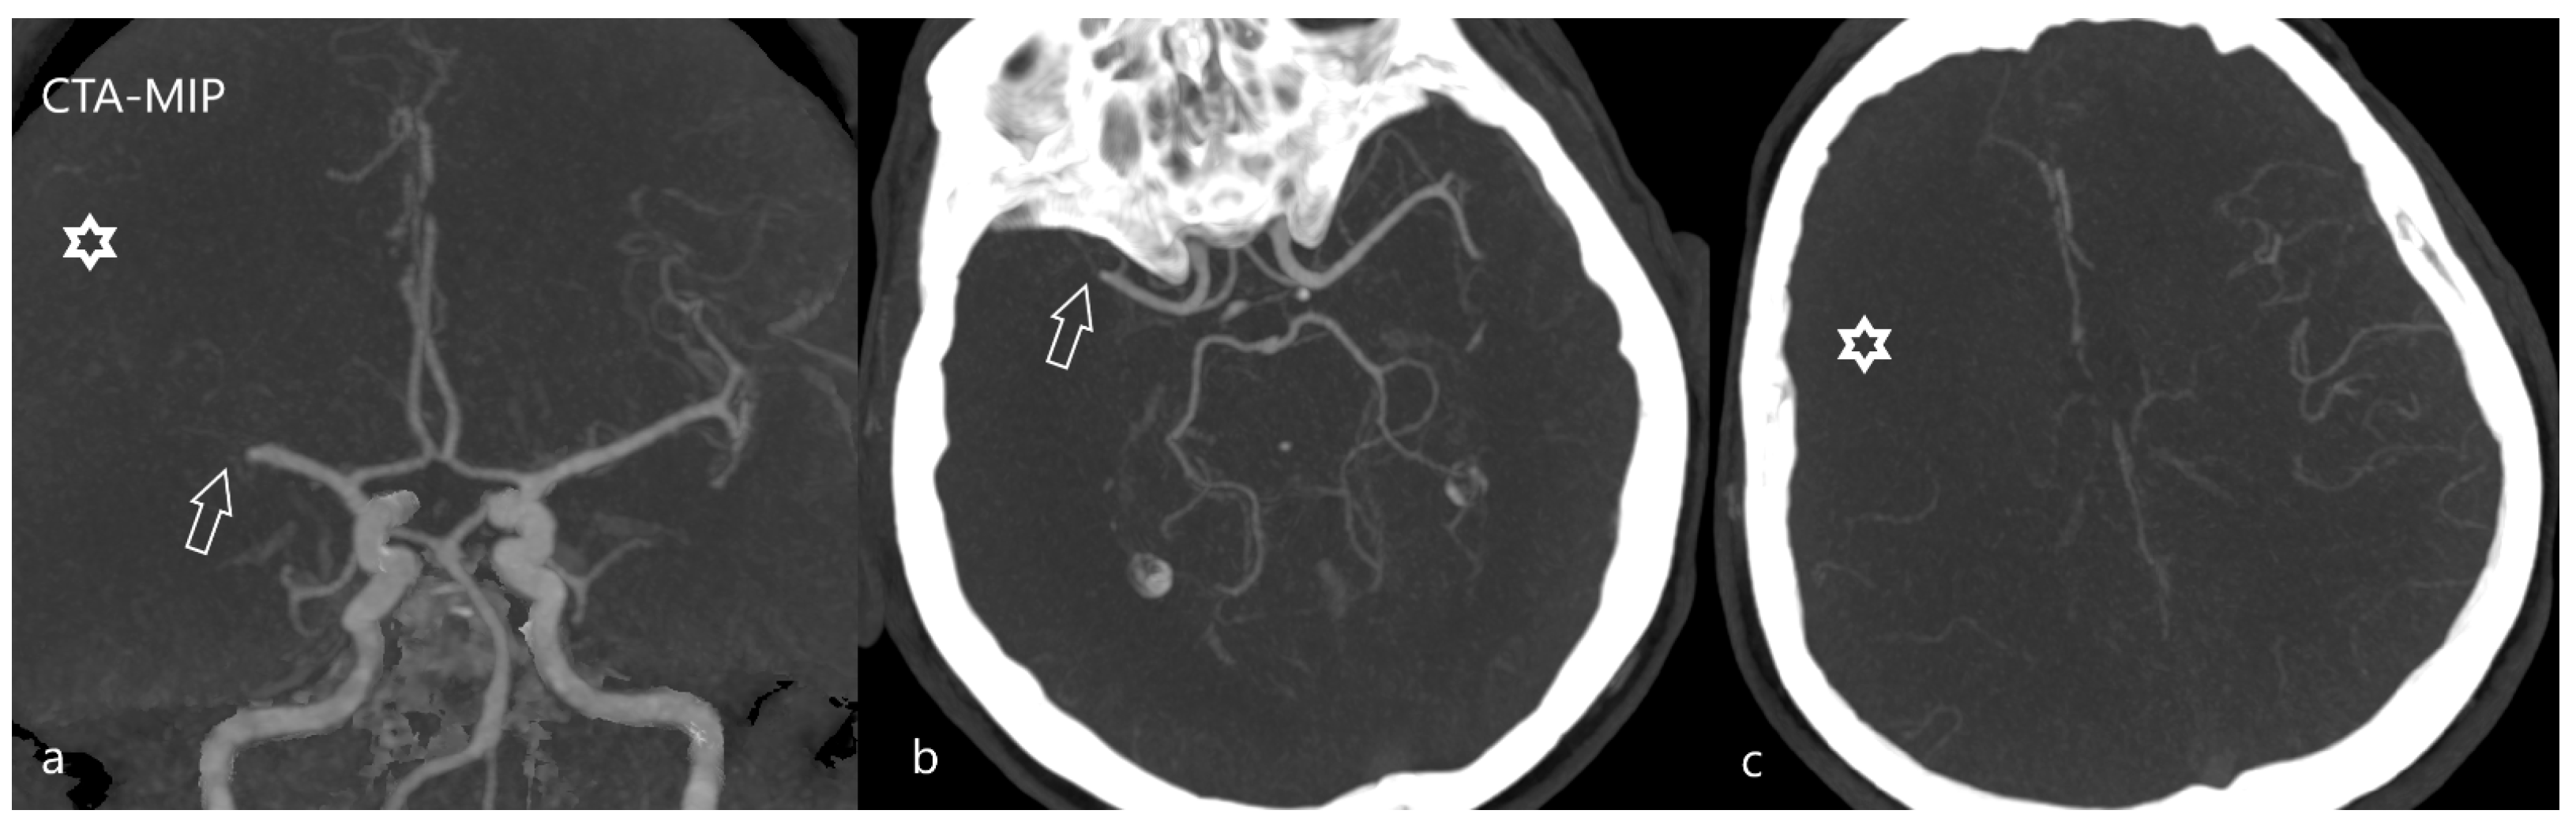

4. Second Task: To Identify Potential Large Vessel Occlusion and Its Localization

- Fasen, B.A.C.M.; Heijboer, R.J.J.; Hulsmans, F.H.; Kwee, R.M. CT Angiography in Evaluating Large-Vessel Occlusion in Acute Anterior Circulation Ischemic Stroke: Factors Associated with Diagnostic Error in Clinical Practice. Am. J. Neuroradiol. 2020, 41, 607–611. [Google Scholar] [CrossRef] [PubMed]

- Walker, B.S.; Shah, L.M.; Osborn, A.G. Calcified cerebral emboli, a “do not miss” imaging diagnosis: 22 new cases and review of the literature. AJNR 2014, 35, 1515–1519. [Google Scholar] [CrossRef]

- Dobrocky, T.; Piechowiak, E.; Cianfoni, A.; Zibold, F.; Roccatagliata, L.; Mosimann, P.; Jung, S.; Fischer, U.; Mordasini, P.; Gralla, J. Thrombectomy of calcified emboli in stroke. Does histology of thrombi influence the effectiveness of thrombectomy? J. Neurointerv. Surg. 2018, 10, 345–350. [Google Scholar] [CrossRef]

- Johansson, E.; Gu, T.; Aviv, R.I.; Fox, A.J. Carotid near-occlusion is often overlooked when CT angiography is assessed in routine practice. Eur. Radiol. 2020, 30, 2543–2551. [Google Scholar] [CrossRef]